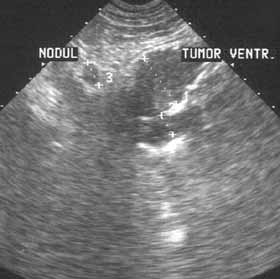

Ультразвуковое исследование в диагностике рака желудка.

Рис. 2. Рак желудка. Метастазы в пригастральных лимфоузлах.

Новости лучевой диагностики 2001 1-2: 37-39